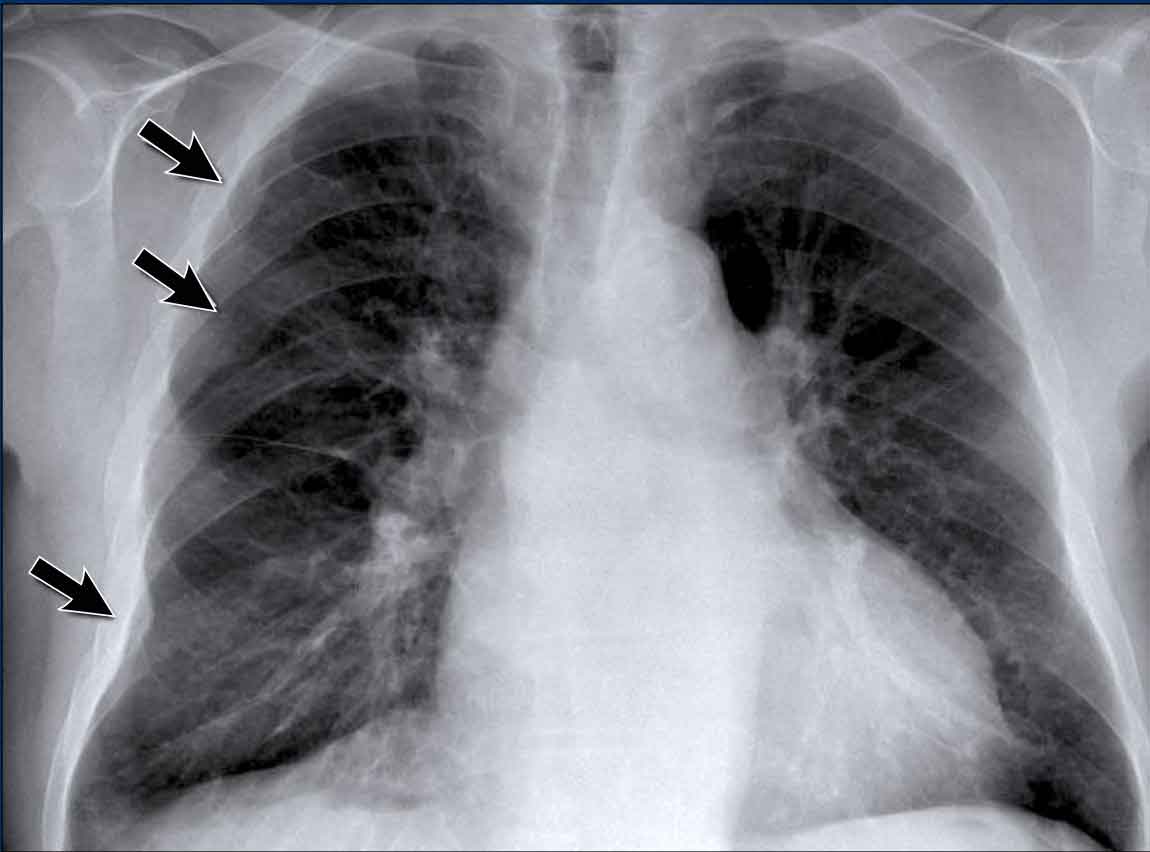

Left Atrial Enlargement

• Patient with a history of chronic mitral valve disease and valve replacement.

• Extreme dilation of the LA leads to bulging of both the right upper cardiac contour (black arrows) and posterior heart border on lateral view (blue arrow).